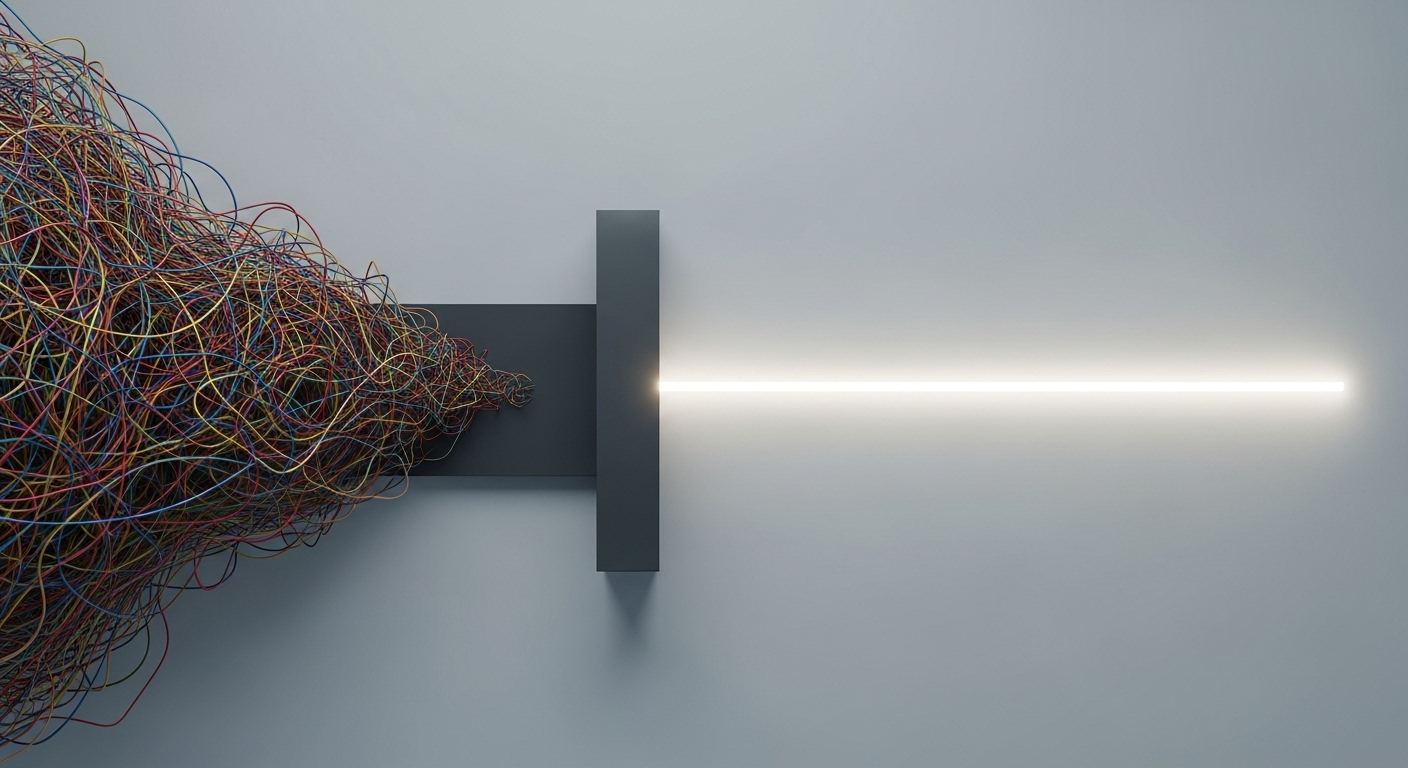

Mais voilà le hic : la quantité d’informations est gigantesque. C’est comme passer d’une simple carte de France à une photo satellite de la Terre entière, où l’on verrait chaque maison. Le plus dur n’est plus d’obtenir l’image, mais de **comprendre ce qu’on regarde**. C’est là que le bât blesse. Les biologistes avaient besoin d’un coup de main pour ne pas se noyer dans cette mer de données.

Deuxièmement, il rassemble tout en un seul endroit. Un des chercheurs, Ruben Dries, explique qu’avant, il fallait jongler avec plusieurs logiciels pour faire une analyse complète. C’était un vrai casse-tête. Giotto Suite a pour but de **rationaliser tout ça**. Et puis, il a été pensé pour gérer des quantités de données de plus en plus grandes, car la technologie ne va pas s’arrêter d’évoluer.